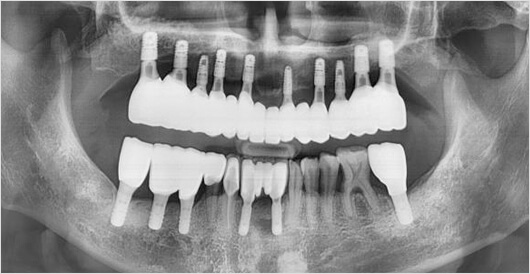

네비게이션 임플란트

0.1mm의 오차도 허용하지 않는 정확함

1. 높은 장기 안정성

2. 교합력 분배로 보철물 파절 방지

3. 보철물 회전이나 탈락 방지

4. 자연치와 가장 비슷한 저작력 회복

5. 심미적인 임플란트 결과